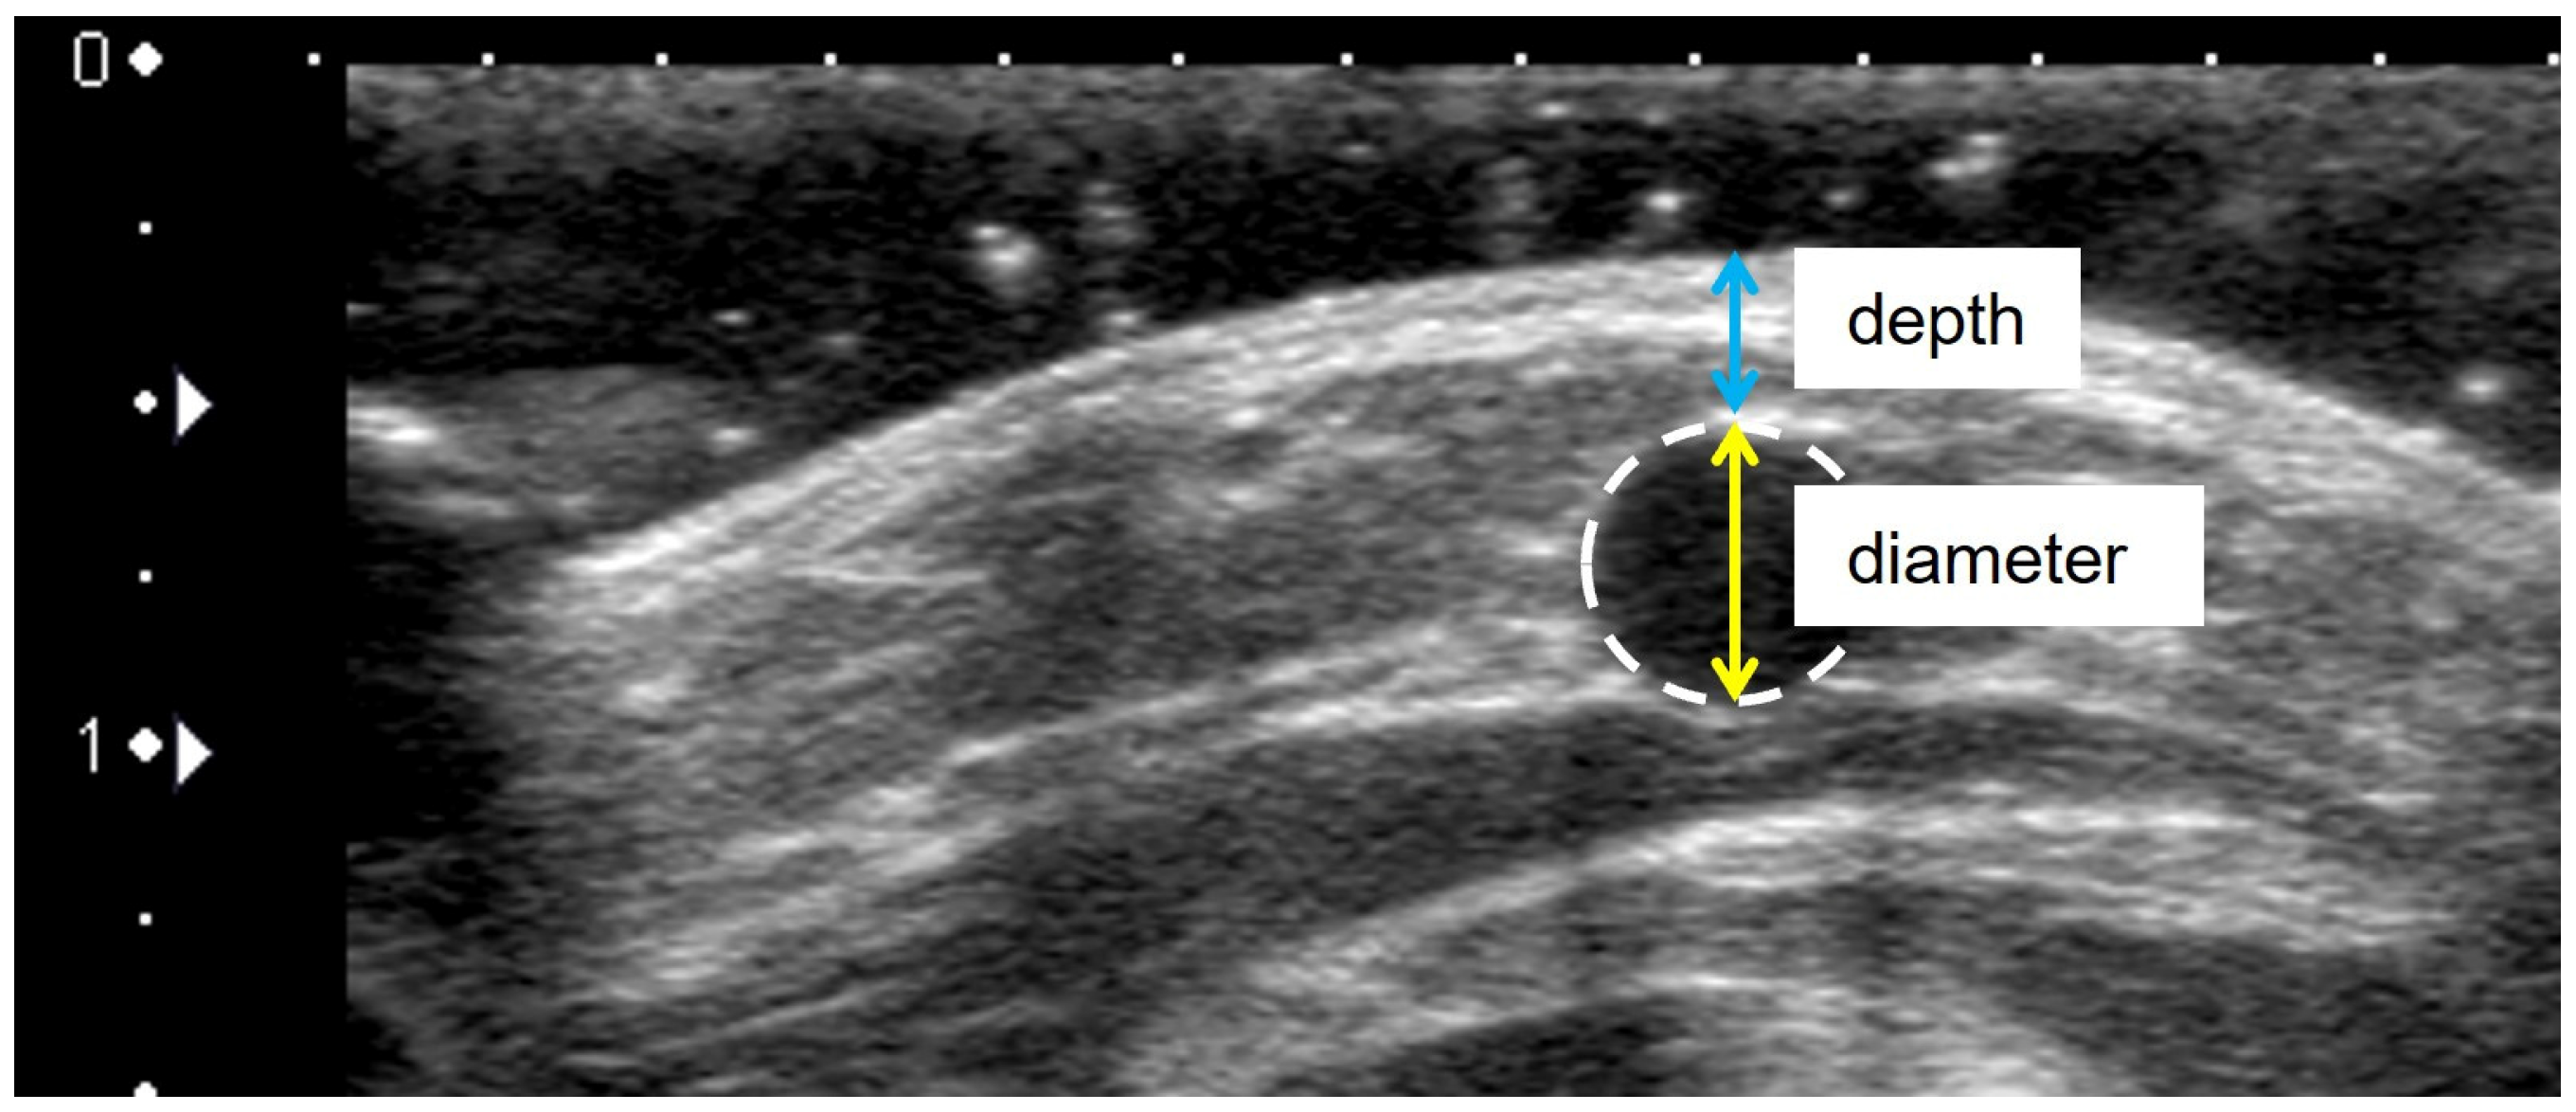

2.7.2. Venous Diameter and Depth

| Venous diameter | - | |

| Venous depth | - | |